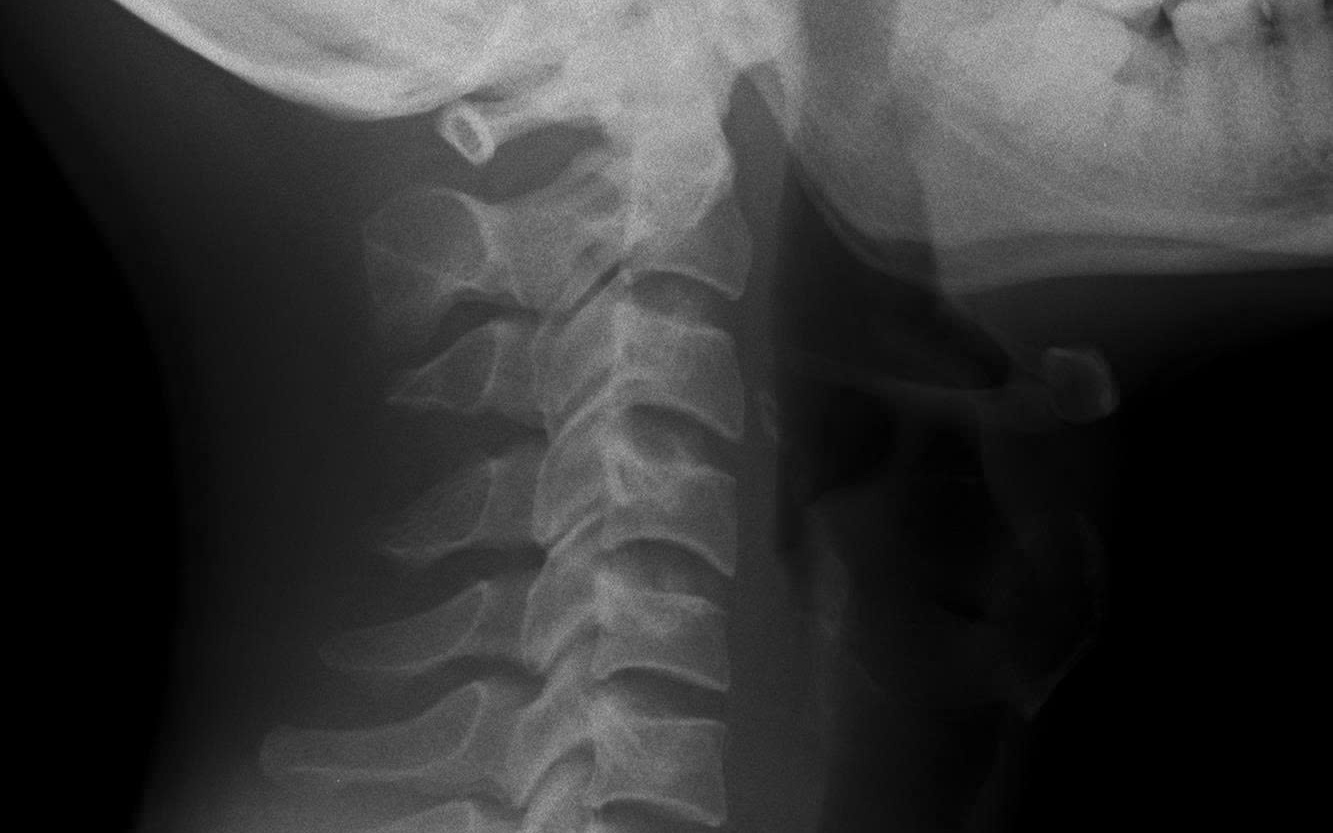

Nhiều người làm công việc văn phòng thường cho rằng, do tính chất công việc văn phòng phải ngồi nhiều, nên bị đau cổ là bình thường. Ở trường hợp này, bệnh nhân dù đã đi khám nhiều nơi, chụp X-quang cột sống cổ và dùng thuốc điều trị đau cổ nhưng tình trạng chỉ đỡ tạm thời rồi tái phát.

Kết quả cho thấy, bệnh nhân bị viêm khớp cùng chậu độ III hai bên, HLA-B27 dương tính, CRP và tốc độ lắng máu tăng. Trong khi đó, X-quang cột sống cổ vẫn chưa có biểu hiện dính khớp hay gai xương.

Theo ThS.BSNT Nguyễn Mạnh Quyết, viêm cột sống dính khớp là bệnh viêm mạn tính, thường gặp ở nam giới trẻ dưới 45 tuổi. Giai đoạn đầu, tổn thương X-quang cột sống có thể chưa rõ, trong khi khớp cùng chậu lại là vị trí bị ảnh hưởng sớm nhất.